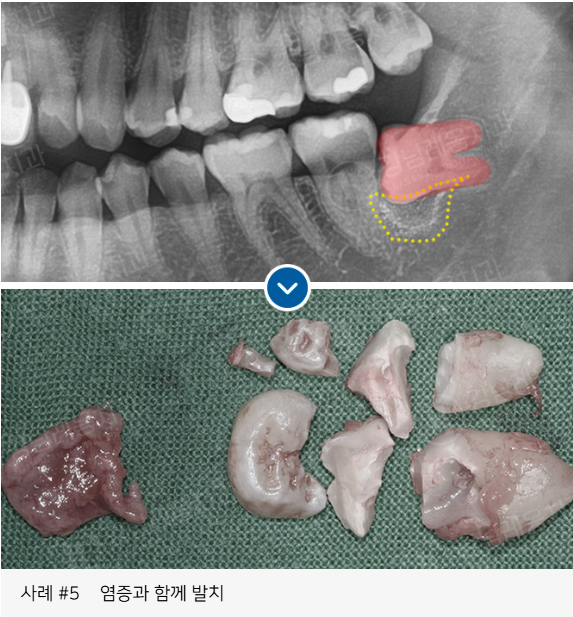

✅ 염증이나 낭종을 동반된 경우

고난도 케이스 경험 다수

사랑니 발치로 강남레옹치과에 방문해주시는

아래와 같은 고난도 케이스도

충분한 상담을 통해

사랑니 진료를 진행하고 있습니다.